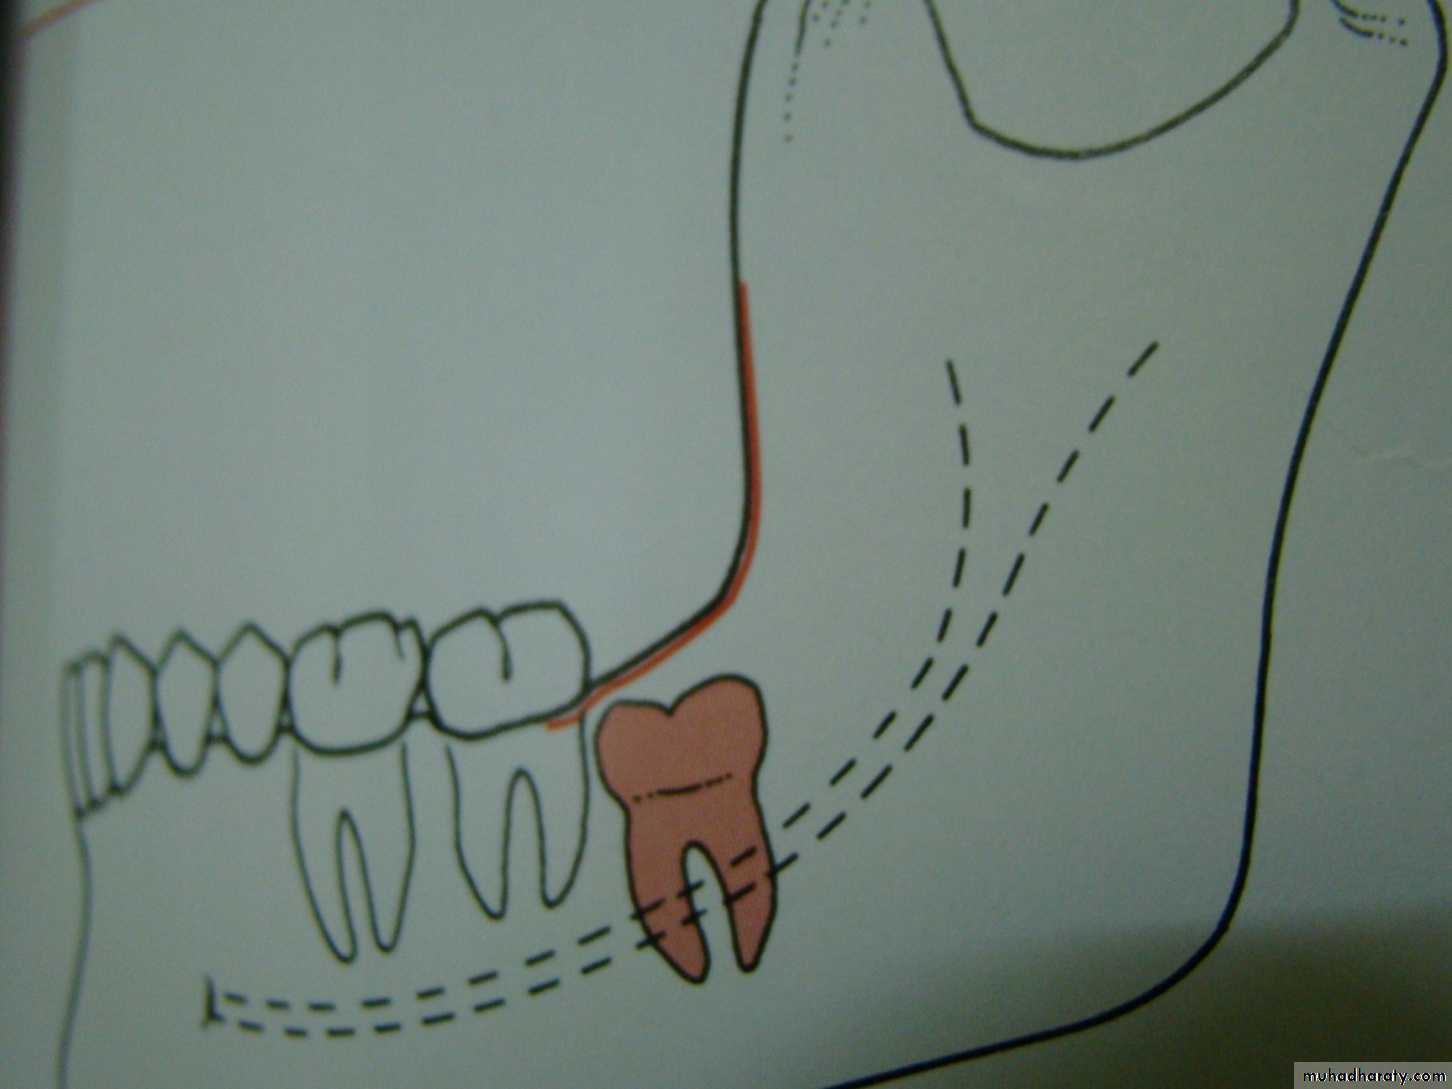

according to the depth

Level A the highest point of the occlusal surface of the impacted tooth lie with or above the occlusal surface of the second molarLevel B the highest point of the impacted tooth lie below the occlusal surface but above the cervical surface of the lower second molar

Level C the highest point of the occlusal surface o f the impacted tooth lie below the cervical line of the lower second molar .